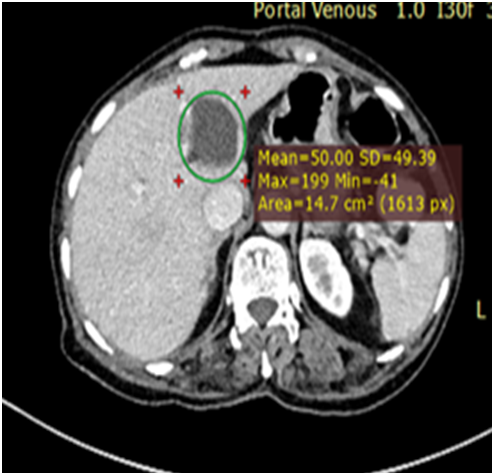

Ultrasound showed a large complex heterogenous pelvic mass likely to be ovarian malignancy. CECT Abdomen was done, which revealed a complex solid cystic lesion in pelvis (11x10x6cm) likely right ovarian malignant malignancy (Figure 1) with multiple heterogenous attenuating masses in liver suspicious of metastasis (Figure 2).

Figure 1 Complex pelvic mass of 11x10cm.

Blood investigation including ovarian tumour markers were normal (S.TSH-3.2Miu/ml, CA 125-42.1, AFP 1.3, Beta hCG(11.1). ECG showed Sinus tachycardia with normal QRS complex. 2D Echo done showed mild PAH, Normal LV function (LVEF 65%). In view of the suspected advanced ovarian malignancy with liver nodule suspicious of metastasis, neo-adjuvant chemotherapy was planned. So FNAC from the liver nodule was done; which showed blood mixed aspirate, no malignancy.